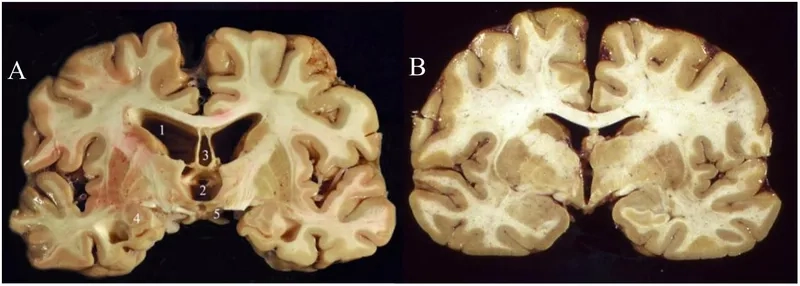

Understanding what causes CTE on a cellular level